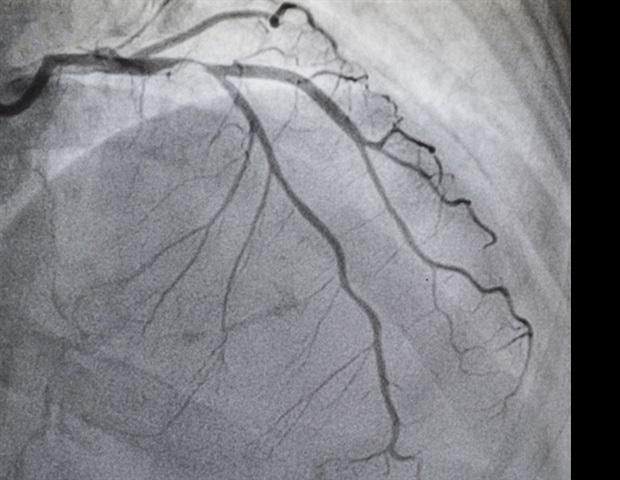

Η αορτική στένωση οφείλεται στη σταδιακή συσσώρευση ασβεστίου, που περιορίζει τη ροή του αίματος. Αποτελεί μία από τις πιο διαδεδομένες και σοβαρές παθήσεις των βαλβίδων, επηρεάζοντας πάνω από 2,5 εκατομμύρια Αμερικανούς άνω των 75 ετών. Τα συμπτώματα, όπως είναι η δύσπνοια, η δυσκολία στη βάδιση και η κόπωση, συχνά παραβλέπονται ως φυσικά σημάδια γήρανσης, με αποτέλεσμα να υπάρχει υποδιάγνωση και υποθεραπεία. Η τυπική θεραπεία είναι η αντικατάσταση αορτής (AVR), που μπορεί να γίνει μέσω ελάχιστα επεμβατικών διαδικασιών ή ανοιχτής καρδιοχειρουργικής.